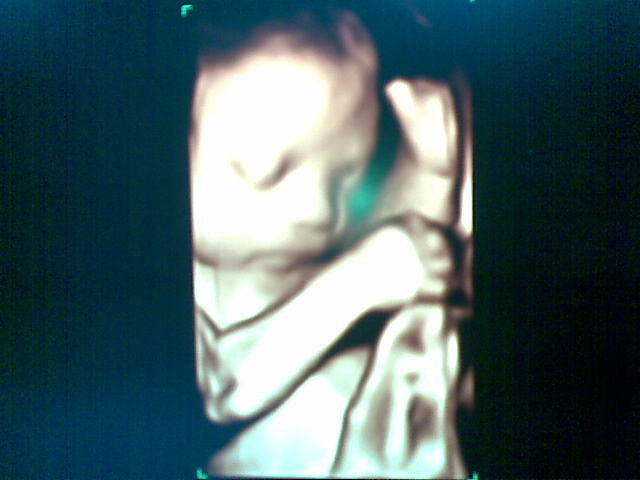

Muke ku yg sembap n nth mcm ape2 di 30 weeks of preggy.. Sungguh x sbr nk potong rambut lps habis pantang nnti..! huhuhu.. 8 more weeks to go.. Moge dipermudahkan segalanya.. InsyaAllah..